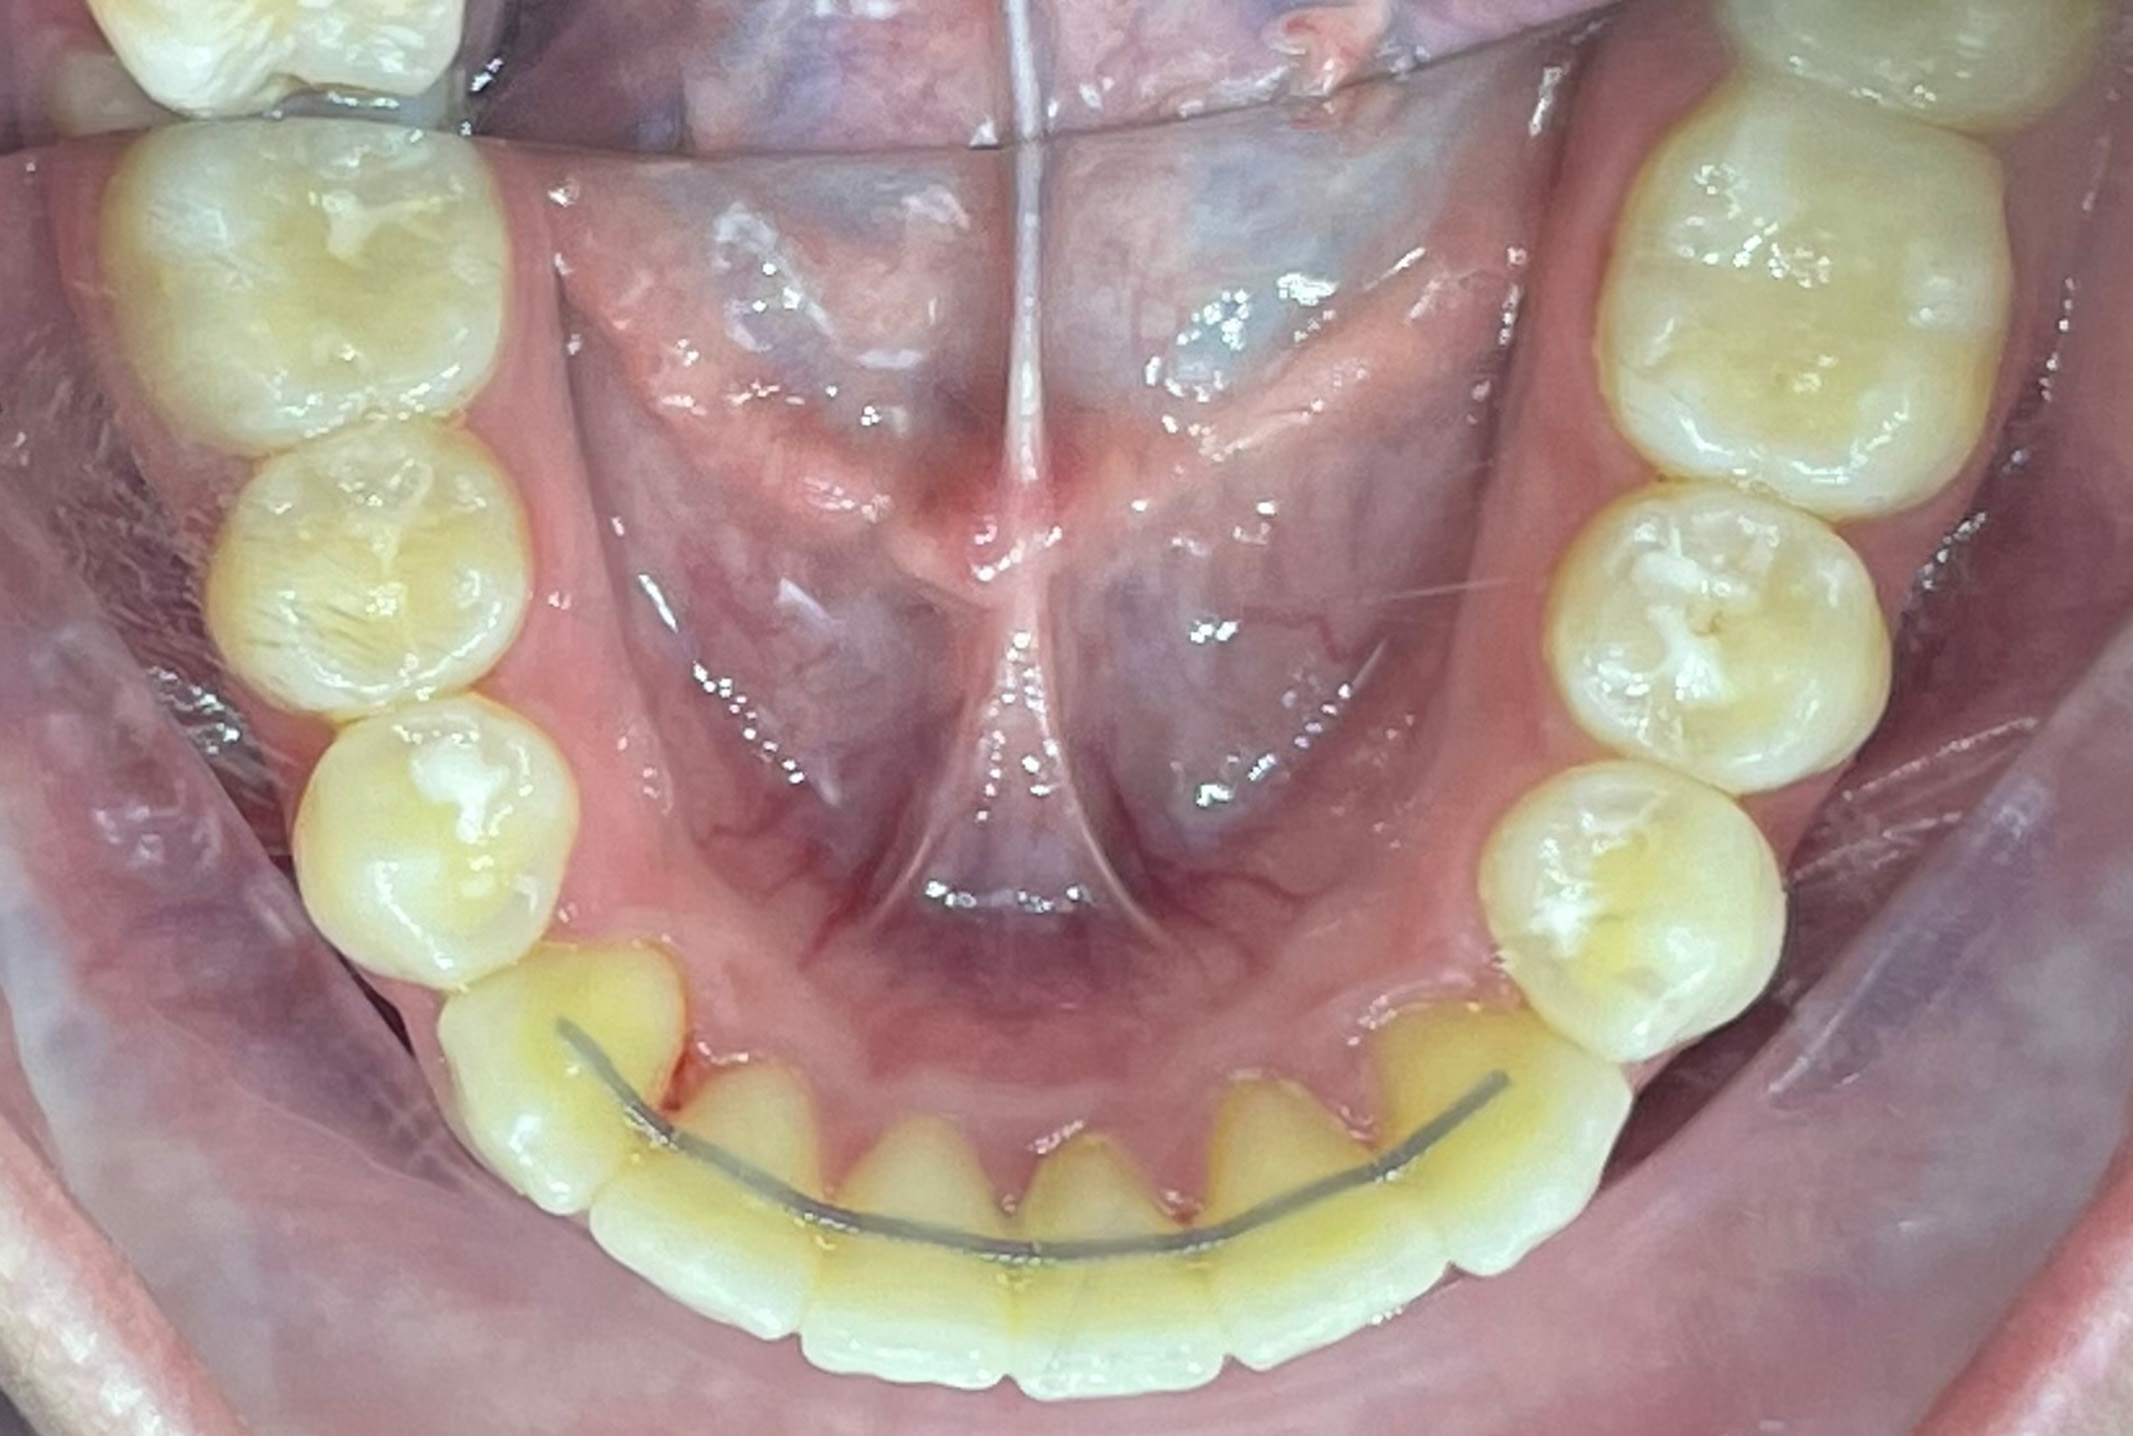

Questo articolo descrive un trattamento con allineatori trasparenti spark eseguito su un paziente di 14 anni con ddm (disarmonia dento- mascellare) moderata, arcate strette, bipro- alveoli e iperdivergenza delle basi ossee.

In primo luogo, il protocollo di trattamento prevedeva lo sviluppo trasversale delle arcate (> 2 mm) al fine di correggere la DDM (disarmonia dento-mascellare) con il protocollo riportato di seguito:

• Espansione delle arcate da 6 a 6, rotazione distale della 6.

• convergenza e rotazione distale di 7.

• È stata aggiunta un’ipercorrezione con 10° di torque della radice vestibolare al fine di evitare la proclinazione di molari e premolari causata dall‘espansione.

Inoltre, sono stati posizionati ritagli di bottoni sui denti 36 e 46 e ganci sui denti 13 e 23 per indossare elastici di classe II (1/4‘ di pollice, forza 4.5 Oz). È stato prescritto un salto antero-posteriore di 1 mm per simulare la crescita mandibolare del paziente. Il dottor Dian ha optato per uno SPARK 20 con 20 allineatori attivi e TruGEN come materiale.